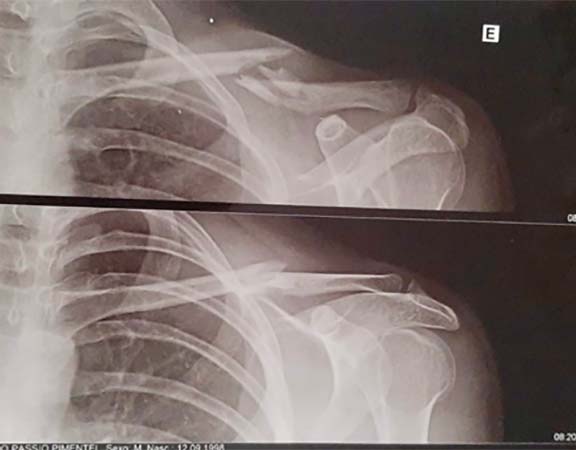

LUXAÇAO DO OMBRO

A luxação do ombro é a perda de contato dos ossos que compõe essa articulação, no caso o úmero e a escapular. Por ser a articulação do corpo humano com maior arco de movimento ela é mais suscetível a luxação, sendo a articulação mais deslocada no adulto. As principais causas da luxação são traumas no ombro ou então por frouxidão ligamentar. Radiografia é o primeiro exame a ser solicitado para se confirmar a lesão. Outros exames como a tomografia e a ressonância também são solicitados para a investigação de outras lesões. O tratamento imediato e a recolocação do ombro no lugar, através de manobras específicas. Alguns pacientes podem evoluir para um quadro de luxação recorrente do ombro, no qual a articulação pode sair do lugar com movimentos simples do dia a dia. Nessas situações o tratamento mais provável é o cirúrgico. O procedimento realizado na grande maioria das vezes é a artroscopia do ombro, entretanto alguns casos podem necessitar de cirurgia aberta ,